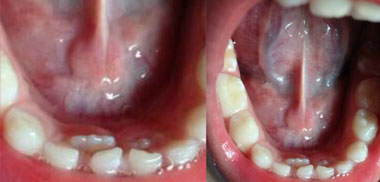

CASO CLINICO

Se observa claramente los centrales inferiores permanente por detrás de los centrales inferiores temporales.

¡Padres! ¿Qué hacer cuando viene un diente permanente y el temporal todavía se encuentra en boca obstaculizando el proceso de erupción del mismo y que este a su vez, ocupe el lugar que le corresponde?

Hay que llevar al paciente al odontólogo lo más pronto posible para extraerle el diente de leche.